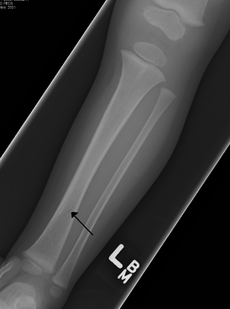

Toddler's fractures or childhood accidental spiral tibial (CAST) fractures are bone fractures of the distal (lower) part of the shin bone (tibia) in toddlers (aged 9 months-3 years) and other young children (less than 8 years).[1] The fracture is found in the distal two thirds of the tibia in 95% of cases,[1] is undisplaced and has a spiral pattern. It occurs after low-energy trauma, sometimes with a rotational component.

Typical symptoms include pain, refusing to walk or bear weight and limping -bruising and deformity are absent. On clinical examination, there can be warmth and swelling over the fracture area, as well as pain on bending the foot upwards (dorsiflexion). The initial radiographical images may be inconspicuous (a faint oblique line) and often even completely normal.[2] After 1–2 weeks however, callus formation develops. The condition can be mistaken for osteomyelitis, transient synovitis or even child abuse. Contrary to CAST fractures, non-accidental injury typically affect the upper two-thirds or midshaft of the tibia.